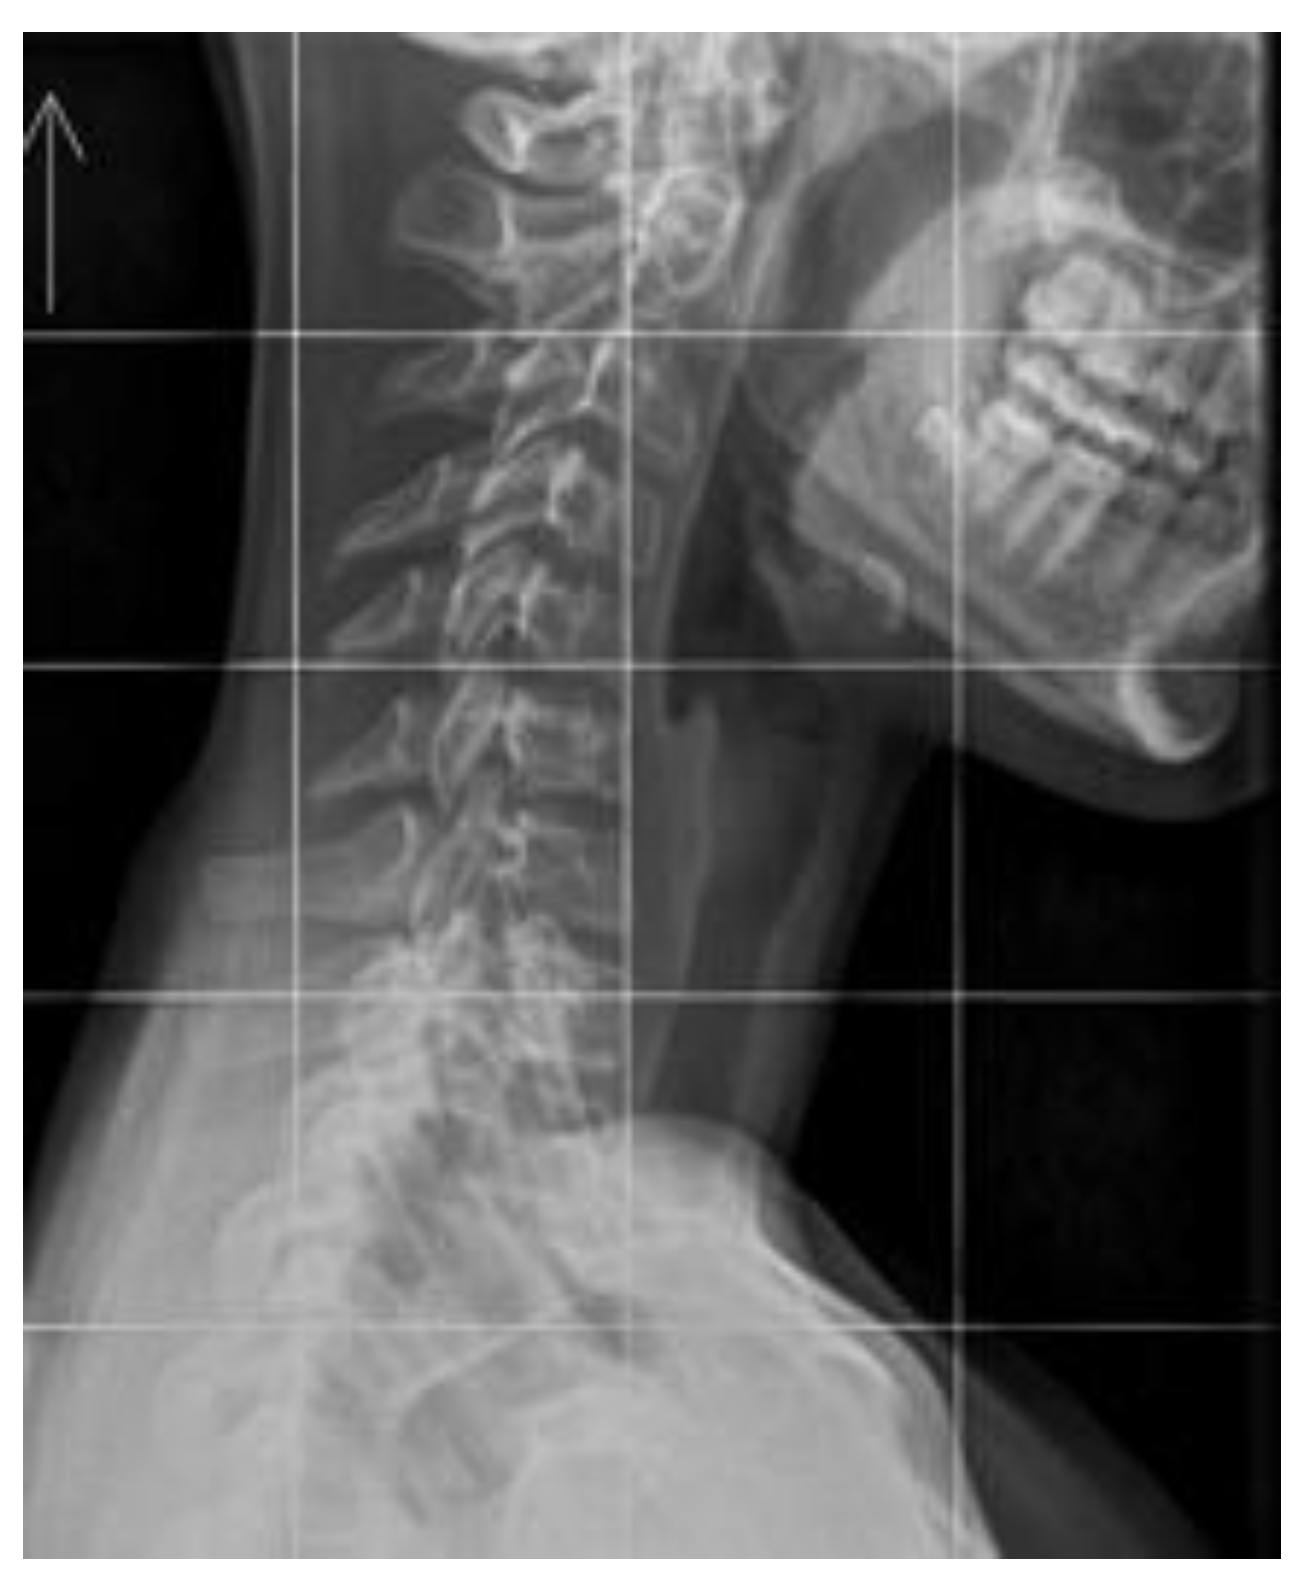

The cervical spine supports the weight of the head while enabling multi-directional movement. This is achieved through the deep muscles of the cervical spine, which aid in perception and stabilize posture, along with the vestibular system and visual input. The upper cervical spine, particularly C1–C3, and the occipitoparietal junction are particularly important. It is estimated that the suboccipital muscles contain a high number of spindles (proprioceptors) [55]. The activity of these mechanoreceptors can be affected by injury, inflammation, or degenerative changes [56]. Changes in loads and impulses in FHP result not only from overloads during work in a head-down position but also from persistent dysfunction. The cervical lordosis loss is a structural disorder that can be seen on neck X-rays in a relaxed, habitual posture (Figure 2 and Figure 3). Muscles have a high capacity to adapt to altered working conditions in non-physiological positions by shortening, atrophy, and degenerative changes. This can impair muscle strength and endurance, creating a vicious cycle whereby incorrect posture leads to changes in muscle morphology and innervation. These changes then cause weakened strength and neurocontrol, which further deteriorate stability and posture. These morphological changes in muscles also cause abnormal, continuous sensory impulses from the paraspinal and suboccipital muscles (deep stabilizers) to the central systems responsible for posture, balance, and coordination, resulting in information noise [56,57].

Figure 2. A symptomatic 17-year-old girl with military neck – chronic headaches, numbness, and weakness of the right hand. Source: File from an outpatient clinic (2025).